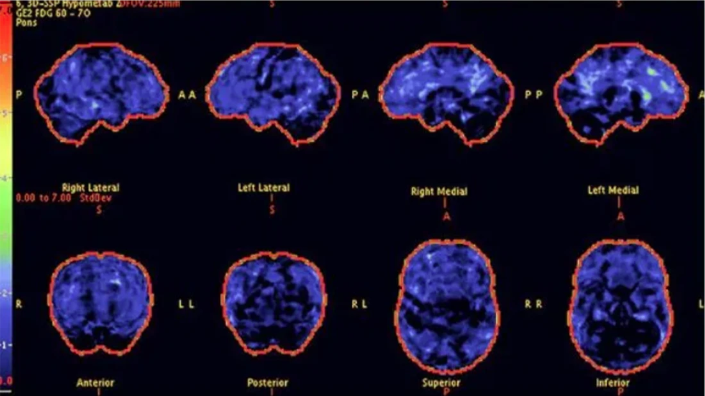

Above: PET scans show reduced brain activity in a 68-year-old woman with progressive symptoms of memory loss. The stained areas indicate low levels of acetylcholine, associated with the accumulation of invisible brain toxins.

Above: After 8 weeks with Memory Lift, PET scans show a significant improvement in brain activity - especially in the areas linked to memory retention and focus. The natural production of acetylcholine has been restored, resulting in greater clarity and cognition.